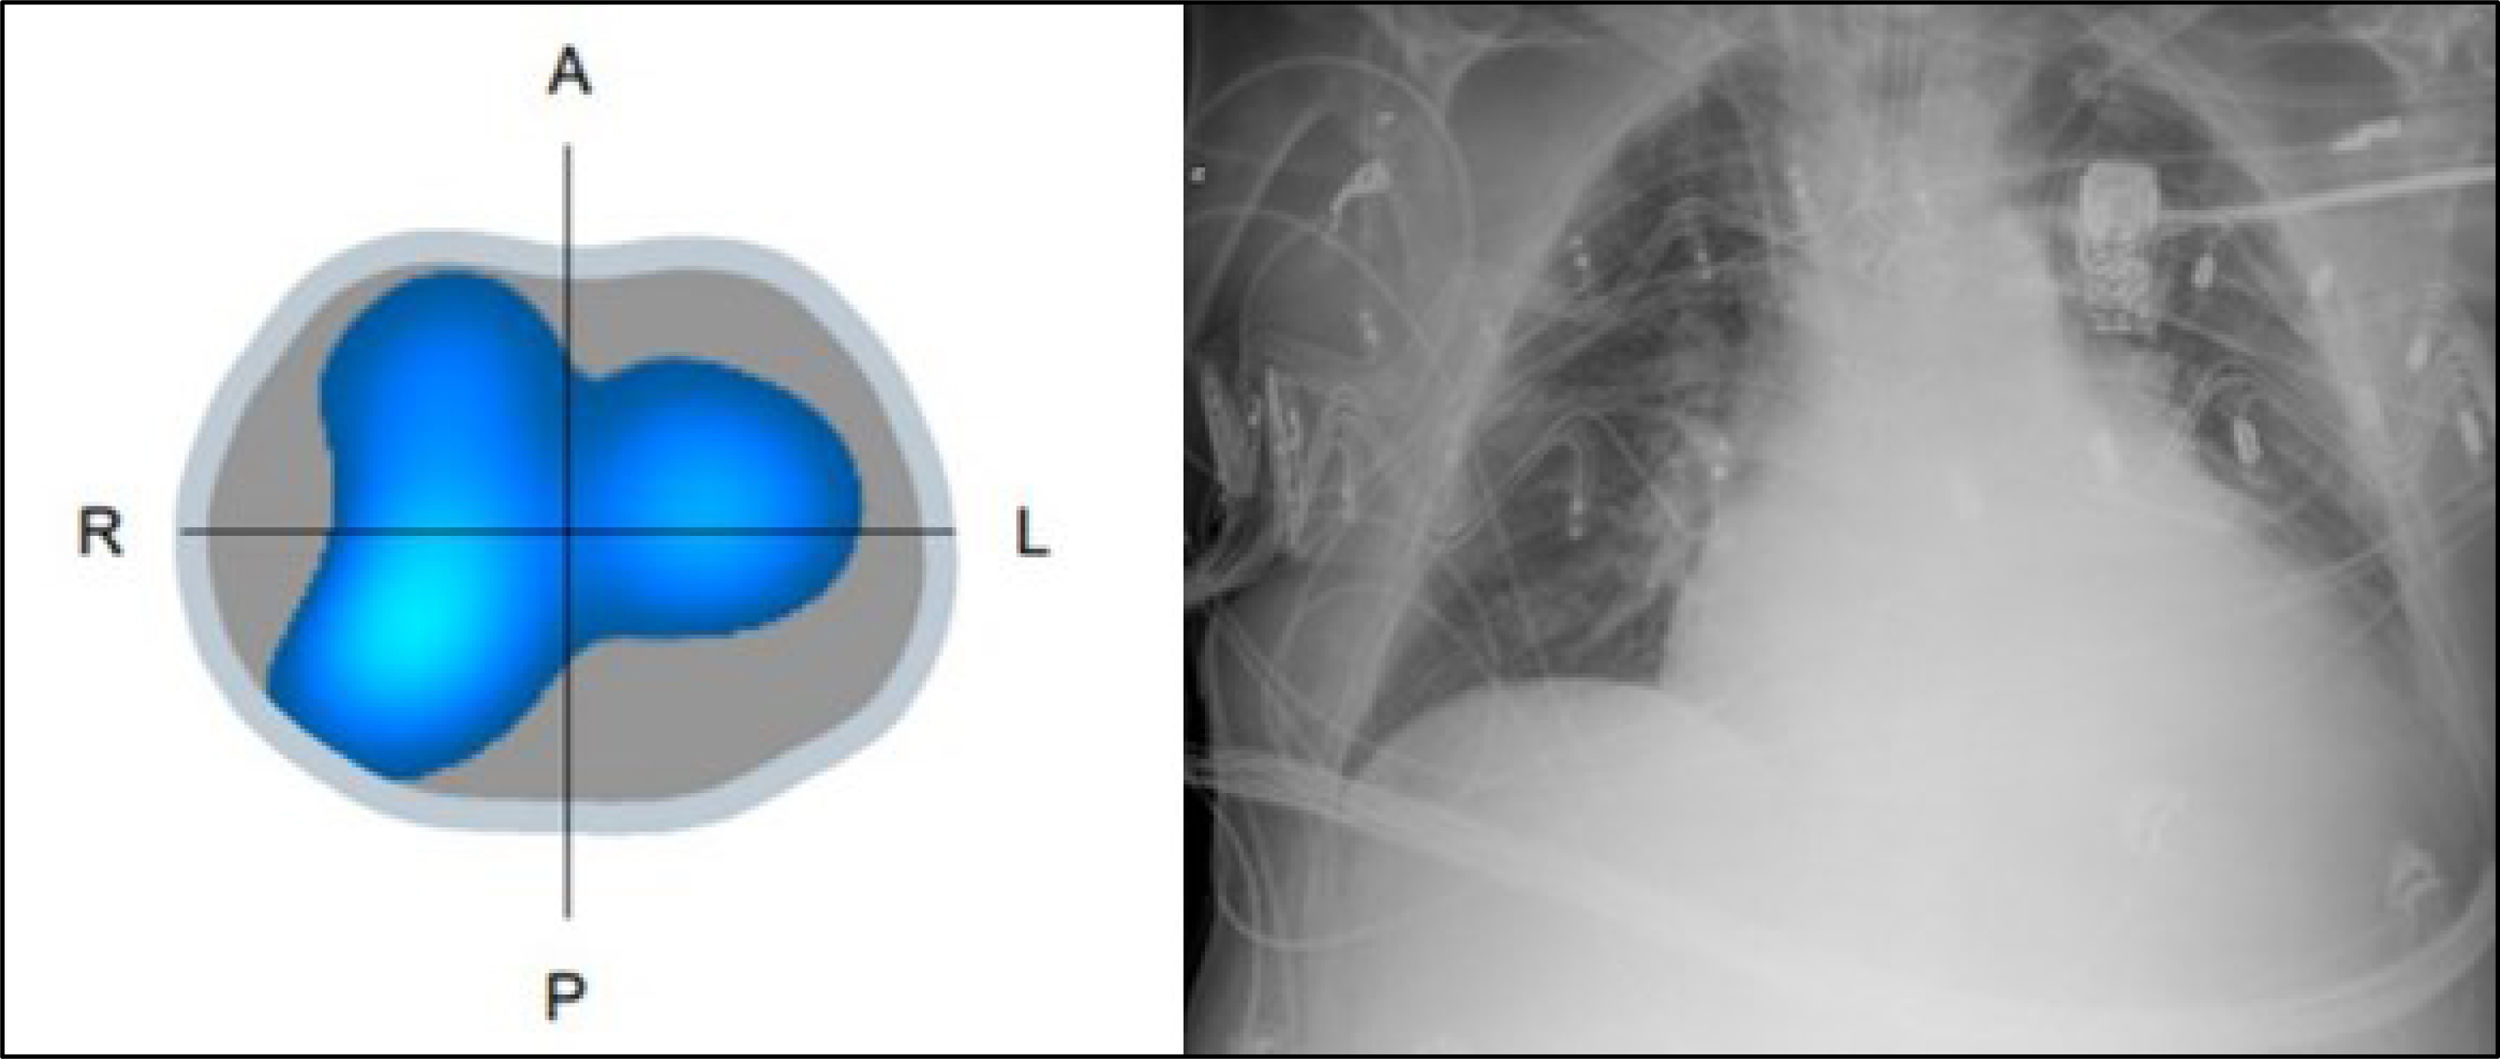

Clinical case presentationA 76-year-old man under invasive mechanical ventilation admitted to the ICU due to pulmonary infection, who presented subtotal left lung collapse during routine postural changes. Trying to recover the left lung ventilation, the patient was repositioned, an endotracheal suctioning and two recruitment manoeuvres were made without any ventilation improvement. The previous level of left ventilation was not achieved until secretions were completely eliminated after three more suctioning manoeuvres.

Discussion and implications for practiceCritically ill patient care is complex, requiring general basic attention and monitoring, including the assessment of the risks that certain interventions and nursing care may entail for each individual patient. Both, postural repositioning and endotracheal suctioning constitutes tow integral parts of routine care for all mechanically ventilated patients. This case shows how the presence of deep secretions during postural repositioning can greatly affect the respiratory function, with no significant immediate or short-term changes observed on routine monitoring, as electrical impedance monitoring is not standard practice, so the changes described in this case would not have been observed in short term.